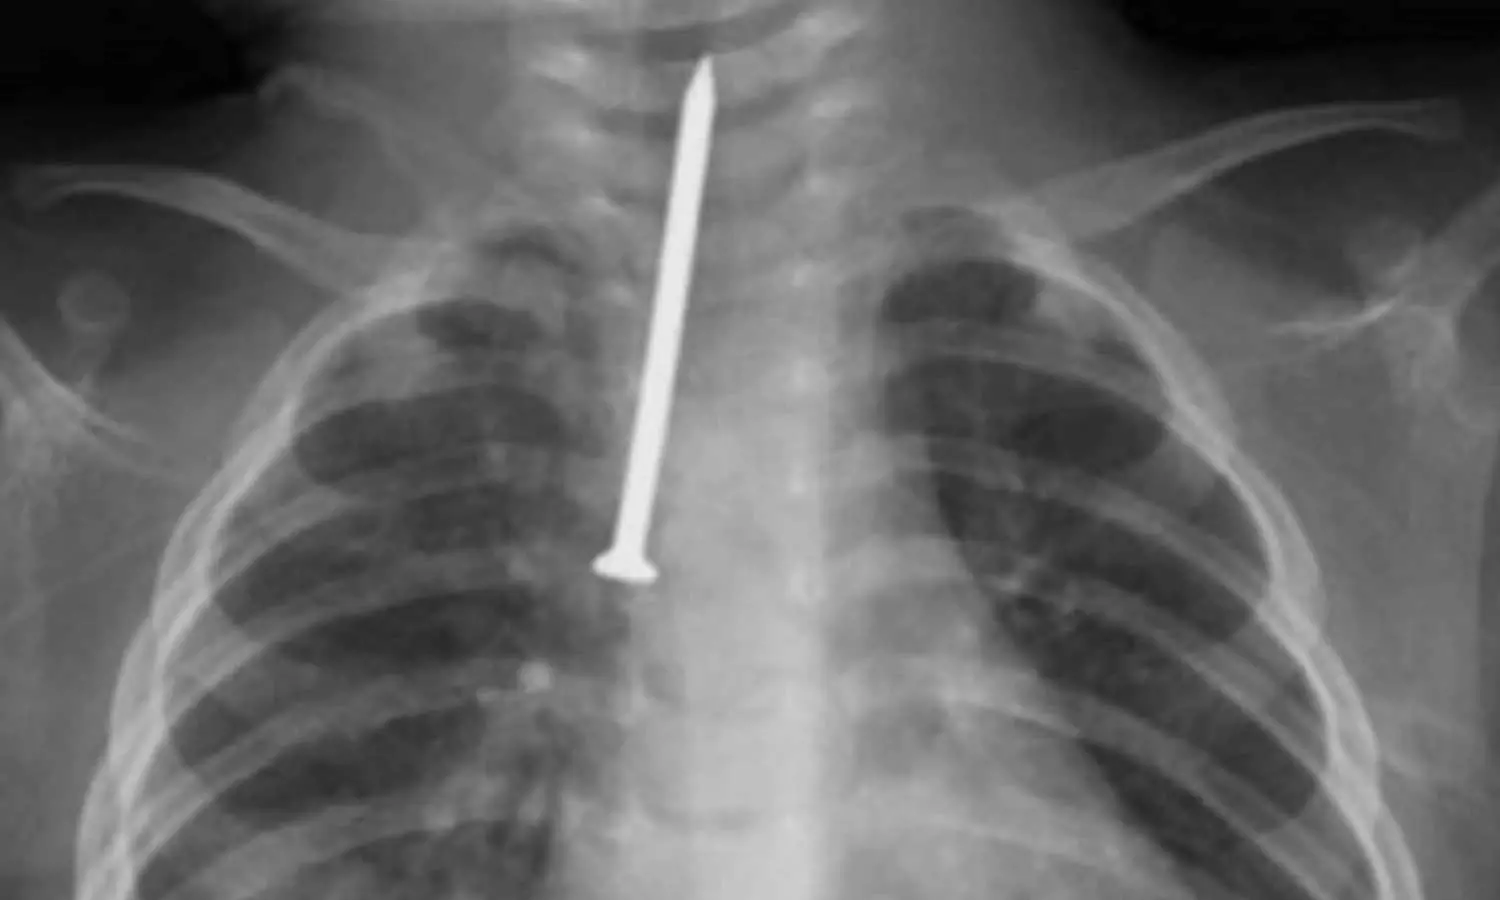

ശ്വാസനാളത്തിൽ കുടുങ്ങിയ ആണി പുറത്തെടുത്തു; റിയാദിൽ എട്ട് മാസം പ്രായമുള്ള കുഞ്ഞിന് പുതുജീവൻ

5 സെ.മീ നീളമുള്ള ആണിയാണ് പുറത്തെടുത്തത്

റിയാദ്: ശ്വാസനാളത്തിൽ അഞ്ച് സെ.മീ നീളമുള്ള ആണി കുടുങ്ങി അതീവ ​ഗുരുതരാവസ്ഥയിലായ എട്ടുമാസം പ്രായമുള്ള കുഞ്ഞിന് റിയാദിൽ പുതുജീവൻ. റിയാദിലെ കിങ് സൗദ് മെഡിക്കൽ സിറ്റി ഹോസ്പിറ്റലിലെ ഡോക്ടർമാരുടെ നേതൃത്വത്തിൽ നടത്തിയ അതി സങ്കീർണമായ ശസ്ത്രക്രിയയിലൂടെയാണ് കുഞ്ഞിന്റെ ജീവൻ രക്ഷിച്ചത്.

അബദ്ധത്തിൽ ആണി വിഴുങ്ങിയ കുഞ്ഞിന് ശ്വസിക്കാൻ കടുത്ത പ്രയാസം അനുഭവപ്പെട്ടതിനെത്തുടർന്നാണ് ആശുപത്രിയിൽ എത്തിച്ചത്. ആണി ശ്വാസനാളത്തിൽ തങ്ങിനിന്നത് കുഞ്ഞിന്റെ നില അതീവ ഗുരുതരമാക്കി. ഉടൻ തന്നെ കുഞ്ഞിനെ ഓപ്പറേഷൻ തിയറ്ററിലേക്ക് മാറ്റുകയും 'റിജിഡ് ബ്രോങ്കോസ്കോപ്പി' എന്ന അത്യാധുനിക സംവിധാനം ഉപയോഗിച്ച് ആണി പുറത്തെടുക്കുകയുമായിരുന്നു. തൊറാസിക് സർജറി വിഭാഗം മേധാവി ഡോ. മുഹമ്മദ് അൽ അംസിയുടെ നേതൃത്വത്തിലുള്ള വിദഗ്ധ സംഘമാണ് ശസ്ത്രക്രിയ നടത്തിയത്.

പിഞ്ചുകുഞ്ഞുങ്ങളിൽ ഇത്തരം ശസ്ത്രക്രിയകൾ നടത്തുന്നതിന് ഉയർന്ന പ്രൊഫഷണലിസവും അത്യാധുനിക ഉപകരണങ്ങളും ആവശ്യമാണെന്ന് ഡോക്ടർമാർ വ്യക്തമാക്കി. കിങ് സൗദ് മെഡിക്കൽ സിറ്റിയിലെ പീഡിയാട്രിക് സർജറി വിഭാഗത്തിലെ വിപുലമായ സൗകര്യങ്ങളാണ് ദൗത്യം വിജയകരമാക്കാൻ സഹായിച്ചതെന്നും അവർ കൂട്ടിച്ചേർത്തു. വിദ​ഗ്ധ ചികിത്സയ്ക്കു ശേഷം കുഞ്ഞിന്റെ ആരോ​ഗ്യനില മെച്ചപ്പെട്ടതായി അധികൃതർ അറിയിച്ചു.